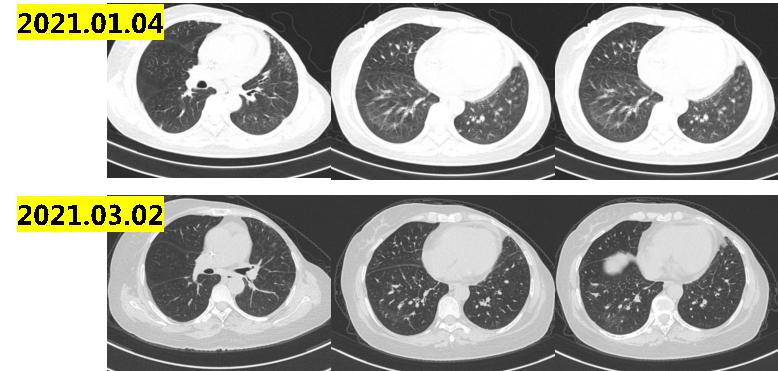

2021.6.10复查肺部ct示:双肺散在实性结节,最大10×8mm,部分病灶较前稍增大;纵隔及肺门淋巴结增大,最大直径13mm(图1-3),考虑病情进展。

图1-3

讨论意见:患者转移病灶瘤负荷低,双肺和纵隔转移数目小于5个,最大直径1.3cm,无内脏危象,建议CDK4/6*制剂抑**联合内分泌治疗。然而进口CDK4/6*制剂抑**患者仍因经济原因无法负担。患者情况符合国产CDK4/6*制剂抑**临床试验入组标准,建议入组:XZP-3287(吡罗西尼)治疗中国晚期恶性实体瘤受试者的多中心、开放性Ⅰ/Ⅱ期临床研究。

2021.06-2021.09入组:XZP-3287(吡罗西尼)治疗中国晚期恶性实体瘤受试者的多中心、开放性Ⅰ/Ⅱ期临床研究,2021.09初患者开始出现胸闷气喘,2021.09.17肺部CT示:双肺下叶炎性病变,双肺下叶小叶间隔增厚,考虑间质性病变;双肺散在结节影,部分同前相仿,部分较前新发,考虑转移可能;心包积液,较前增多。示双肺及叶间裂胸膜处多发小结节,较前新发,考虑病情进展(图1-4)。

图1-4